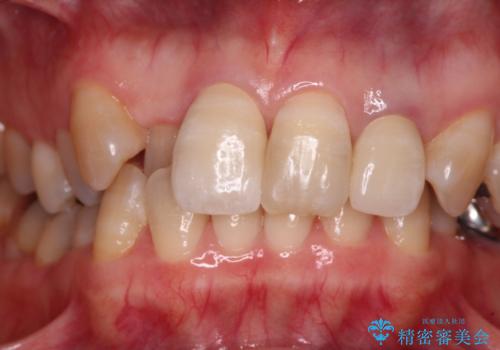

オールセラミッククラウンは周囲の歯よりもやや白く製作し手降りますが、今後はご自身でホワイトニングをして明るい色調で整えるとのことでした。

レントゲン写真より、歯根の炎症が認められなかったため、ファイバーコアによる土台築製後、オールセラミッククラウンにて補綴することとしました。

また、真ん中の前歯はコンポジットレジンによる修復跡が目立っており、合わせてオールセラミッククラウンにて治療することとしました。